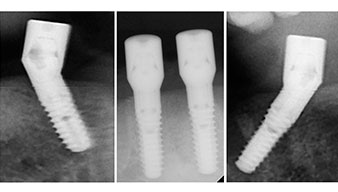

Направи се скенер с триизмерна компютърна томография (CBCT, Planmeca), за да се подпомогне планирането и да се намалят рисковете. Той показа, че качеството и количеството на наличната кост са достатъчни за операцията и имедиатното възстановяване, използвайки Fast & Fixed метод. Следвайки протокола за тази концепция, имплантите са поставени на 35, 32, 42 и 45 позиция. Ангулирането на дисталните импланти до 45° промени профила в задната зона и осигури по-голяма поддръжка в многоъгълната зона (Фиг. 3).

Fast & Fixed метод

Фиг. 3